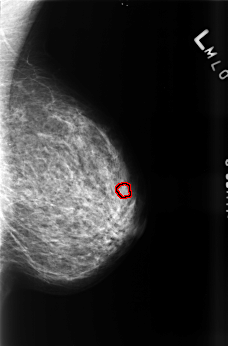

B_3460_1.LEFT_MLO

FILE: B_3460_1.LEFT_MLO.OVERLAY

TOTAL_ABNORMALITIES 1

ABNORMALITY 1

LESION_TYPE CALCIFICATION TYPE PLEOMORPHIC DISTRIBUTION CLUSTERED

ASSESSMENT 4

SUBTLETY 3

PATHOLOGY BENIGN